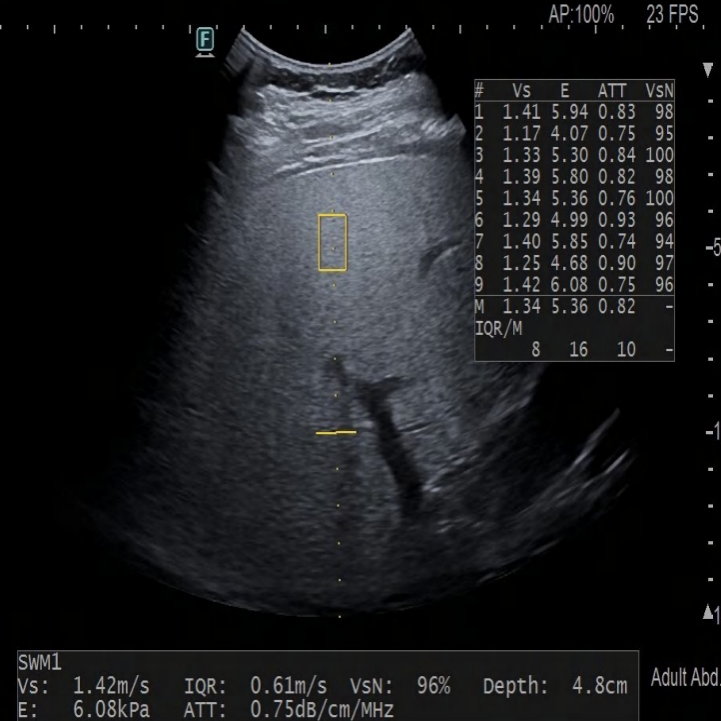

(健康儿童(左图)与脂肪肝儿童(右图)的肝弹性超声图像)

温馨提醒:有时候娃儿肝脏发炎、肚子胀气厉害,可能会影响报告结果,所以千万别仅凭报告上的数字,就判断娃的病情,一定要听医生的专业意见哦!